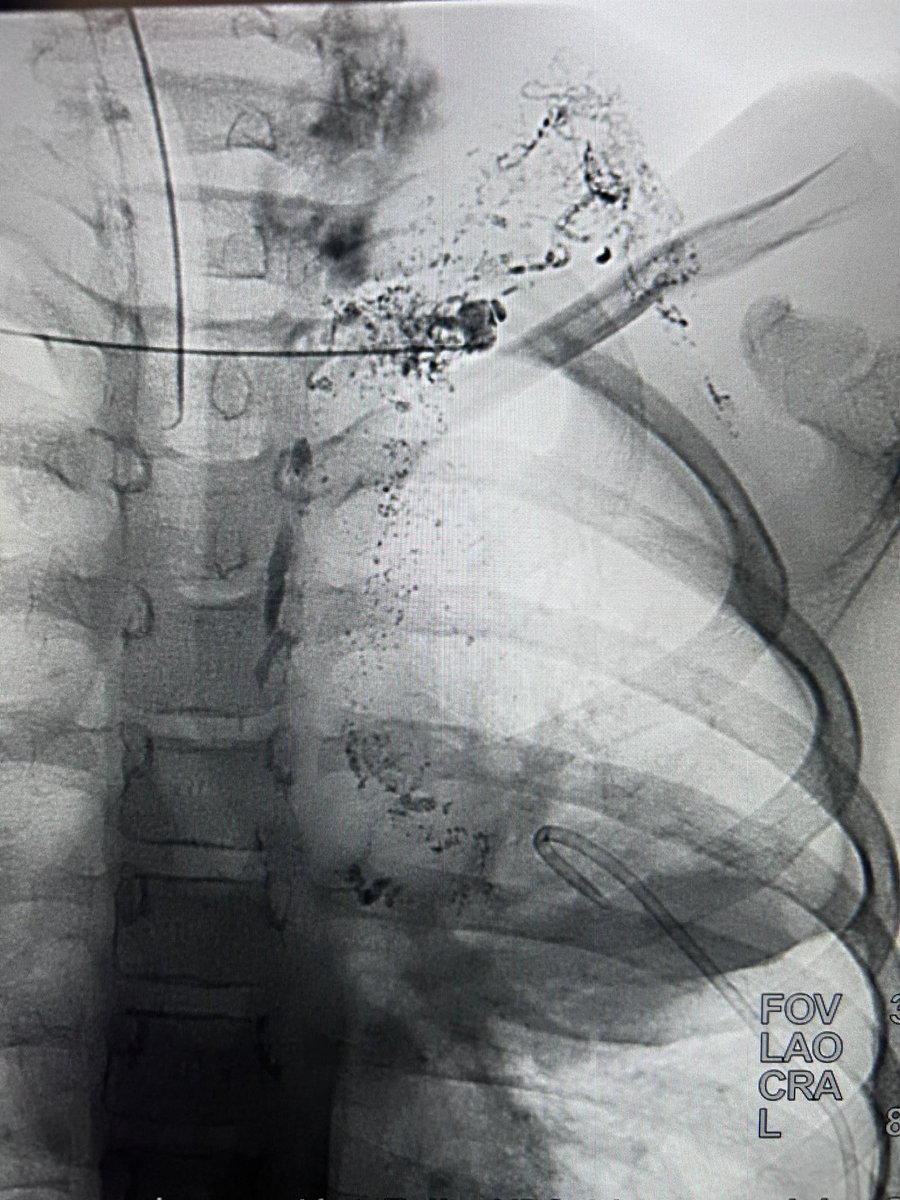

Case 75: with @BhaveshPopat7 . Intranodal Lymphangio(INL)+Thoracic Duct Embo(TDE): coil+glue for chylous pericardium sec to ALL . #irad #medtwitter #cardiotwitter @SriniTummala @TheRealDoctorOs @keithppereira @FadiSaab17 @t_intheleadcoat @SRajesh_IR @IR_Juniors @iRadBIR_Chennai